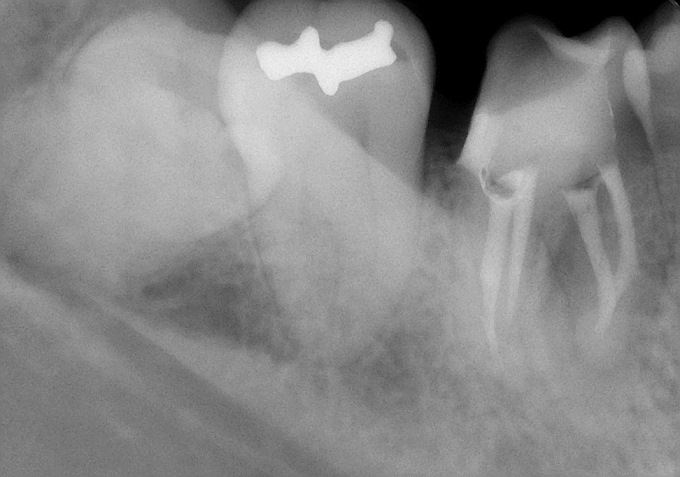

レントゲン写真で確認すると

根の先に病気がある。かぶせ物の適合も悪そう。

そして・・・

う~ん・・・(汗) どうも治療器具が折れて中に残っていそう(T_T) そのため、根の先まで治療が行えていない。